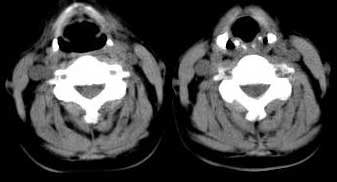

女 48岁 无意中发现左侧颈部肿块

甲状腺左侧叶下部结节状低密影,边界较清晰,考虑甲状腺肿瘤[腺瘤可能性大,恶性待排]

甲状腺左叶低密度病灶,边界尚清楚,邻近气管、血管、肌肉无明显侵润;考虑良性病灶,以甲状腺腺瘤可能大。

左侧甲状腺下极可见类圆形结节样低密度病灶,边缘清晰,未见明显周围组织受侵,颈部未见明确淋巴结肿大;右侧甲状腺形态密度未见异常。

诊断意见:左侧甲状腺结节样病灶,多考虑甲状腺腺瘤。建议ect检查。